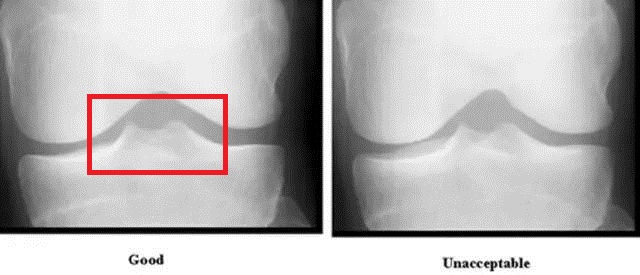

关节软骨

软骨(想想吃的猪脆骨,或者田鸡)是一种薄而有弹性的结缔策划,通过吸收震动来保护骨骼。软骨还可以确保关节表面很容易地相互滑动,使膝盖的运动更加顺畅。

所有构成膝关节的骨头都有关节软骨或透明软骨覆盖在每个骨表面的末端。

关节软骨的损伤通常是由过度使用、老化引起的渐进性“磨损”损伤。